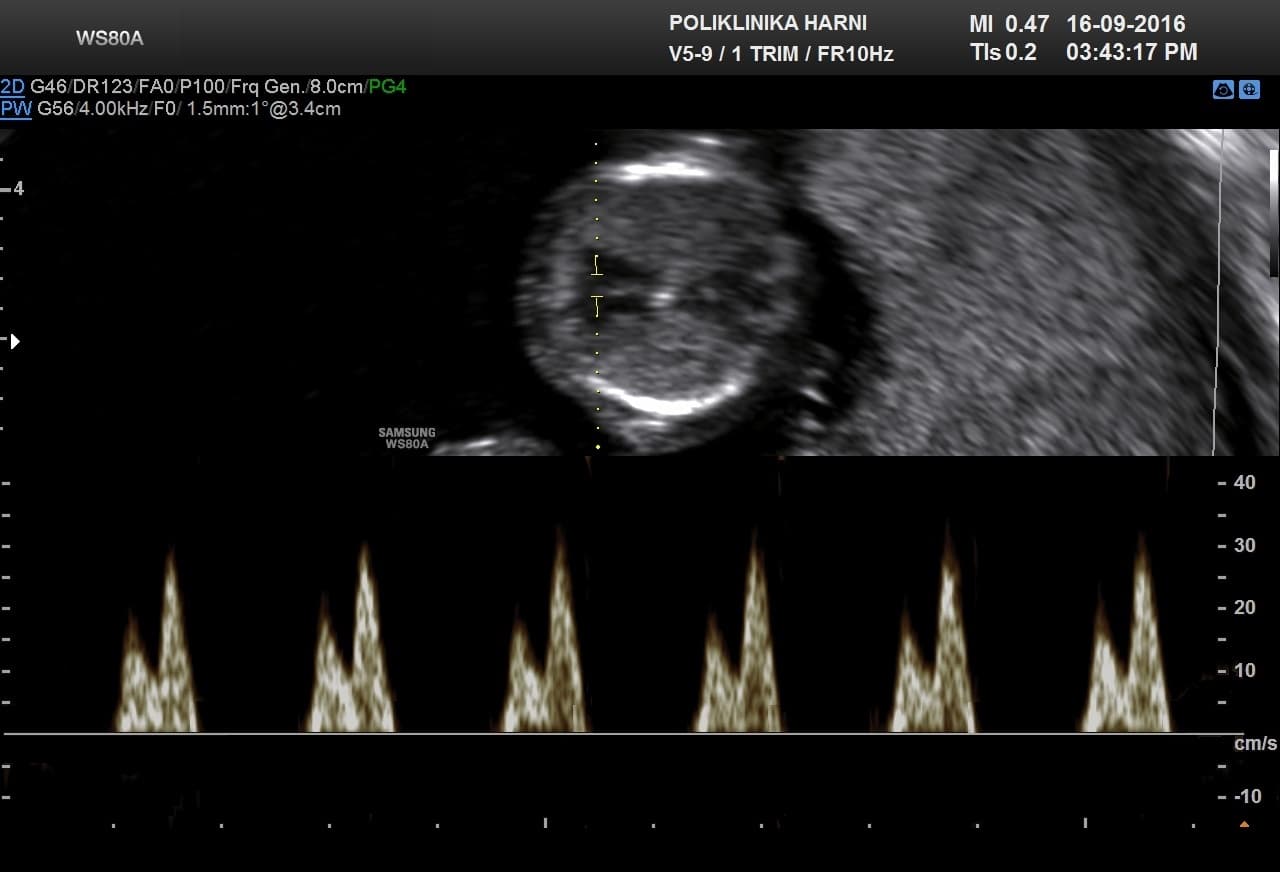

Radi se o specifičnim ultrazvučnim pokazateljima koji ne spadaju u anomalije već prije prolazne pojave u trudnoći. Obuhvaćaju ne samo debljinu nuhalnog nabora, već i prisutnost nosne kosti, lični kut, nalaz dvije umbilikalne arterije, procjenu protoka kroz duktus venozus tijekom atrijske kontrakcije i nalaz trikuspidalne regurgitacije. Procjenjuju se prema strogim kriterijima koje je propisao FMF – Fetal Medicine Foundation, London, između 11. i 13+6 tjedna trudnoće kada je duljina tjeme-trtica između 45 - 84 mm. Ovaj ultrazvučni pregled je poznat i pod nazivom mini-anomaly scan.